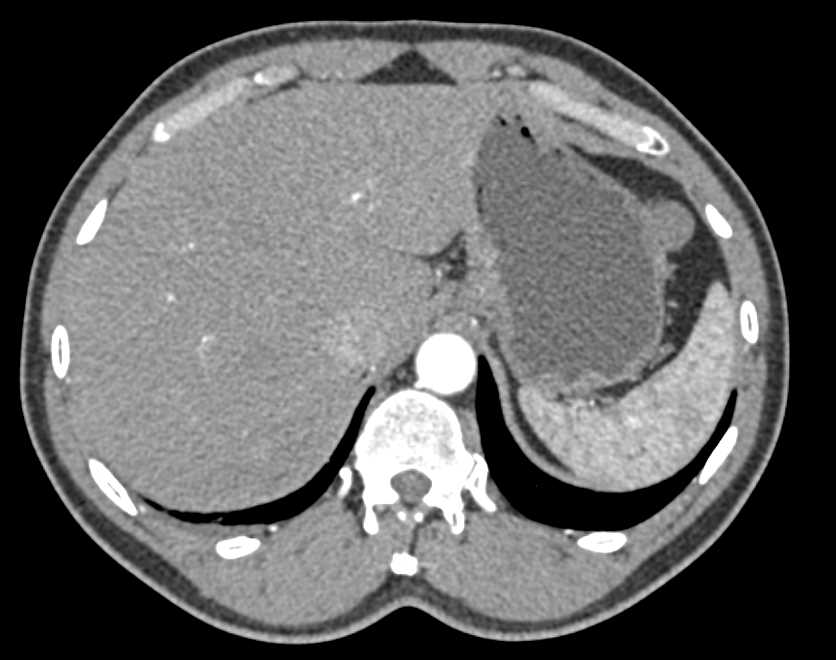

2cm Gastric GIST Tumor